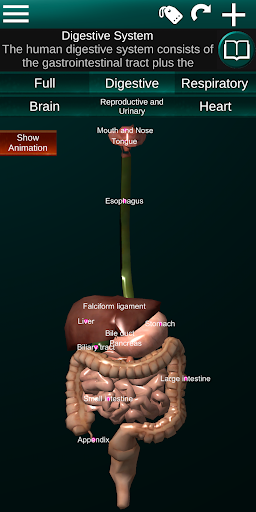

Показує 3D анатомічну модель основні органи людського тіла та опис кожного з них.

* Травна система, включаючи шлунок, тонку кишку, товсту кишку та анімацію цієї системи.